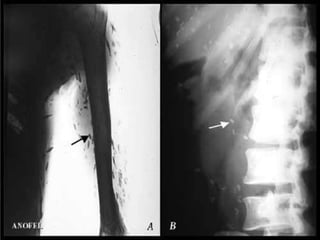

sous-arachnoïdiennes les kystes peuvent atteindre 10 cm et plus, car leur développement n’est pas limité par la pression intracérébrale, - spinales ou médullaires, localisées soit dans la moelle, soit dans les espaces arachnoïdiens.

sous-arachnoïdiennes les kystespeuvent atteindre 10 cm et plus, car leur développement n’est pas limité par la pression intracérébrale, - spinales ou médullaires, localisées soit dans la moelle, soit dans les espaces arachnoïdiens.